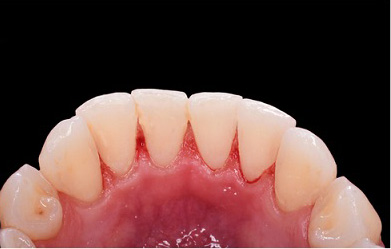

The best way to prevent gum disease is effective daily brushing and flossing as well as regular professional examinations and cleanings. Unfortunately, even with the most diligent home dental care, people still can develop some form of periodontal disease. Once this disease starts, professional intervention is necessary to prevent its progress.

The initial stage of treatment for periodontal disease is usually a thorough cleaning that may include scaling or root planing. The objective of these non-surgical procedures is to remove etiologic agents such as dental plaque and tartar, or calculus, which cause gingival inflammation and disease. Scaling and root planing can be used as a stand-alone treatment, or a preventative measure. They are commonly performed on cases of gingivitis and moderate to severe periodontal disease.

Finally, scaling and root planing may make the mouth more aesthetically pleasing, and should reduce bad breath caused from food particles and bacteria in the oral cavity. Superficial stains on the teeth will be removed during scaling and planing, adding an extra bonus to the procedures.